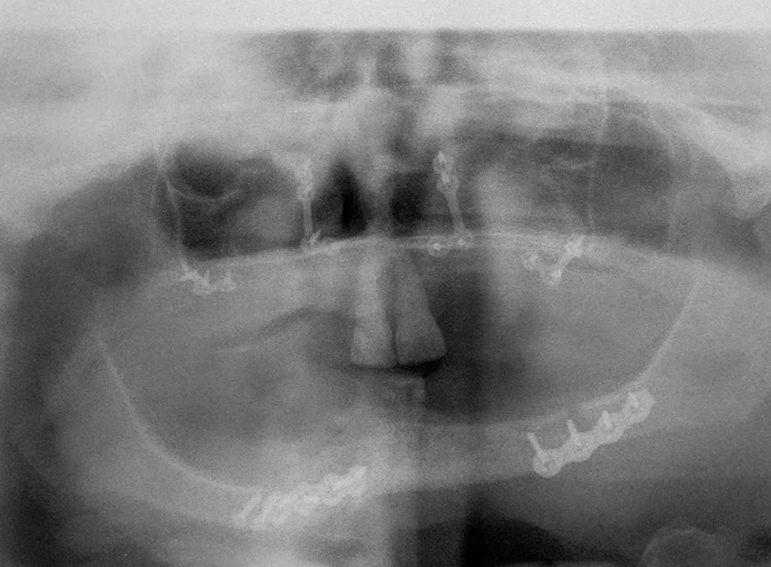

Upper and lower dentures (with implants) after broken jaws.